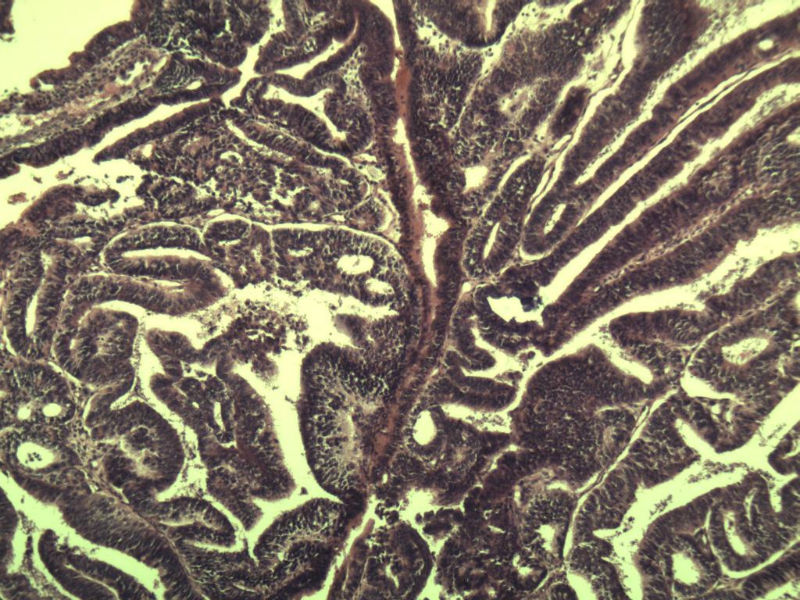

女 32岁 不规则阴道流血 一年  请各位老师看看 谢谢了

遵义医学院附属医院会诊结果    "复杂性增生伴非典型性 "

补充一下病史 病人10个月前因月经不规则行诊刮 诊断非典型性增生  上了曼月乐避孕环(好像是缓慢释放孕激素的那种),         都用激素治疗大半年了 还是这个样子 我还是觉得是癌  只有追踪一下以后病人的情况吧

高分化子宫内膜样癌

非典型复杂性子宫内膜增生,应了解雌孕激素情况。

子宫内膜复杂性非典型性增生,局灶区间质肉芽样(图5)及蜕膜样变,不够癌,建议临床查激素水平并追踪。

从照片看,没看到浸润的地方,我考虑是子宫内膜重度不典型增生。